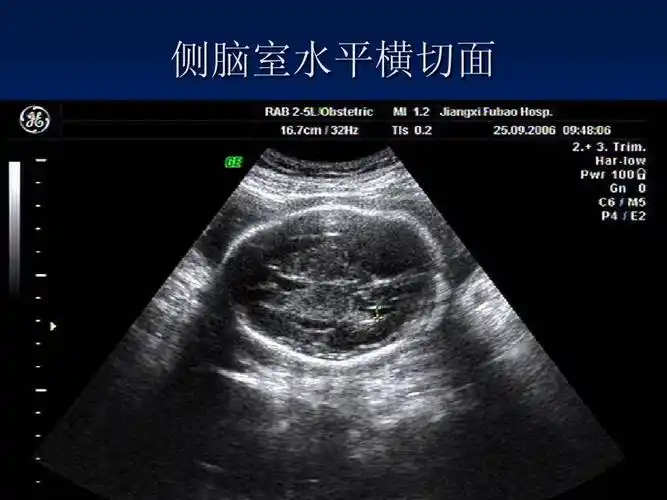

无忧文档 所有分类 医药卫生 临床医学 产科超声技术操作规范ppt 第7